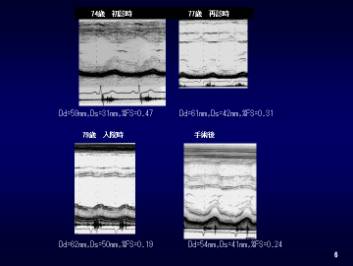

70歳頃より心雑音を指摘されるも無症状のため放置していた。74歳時白内障手術の際、大動脈弁狭窄症の診断を受けた。大動脈弁を通過する血流速は3.5m/secでA/E>1であった(図6-8)。77歳頃より夜間に強い咳が出現し始め、大動脈弁を通過する血流速は5m/secと増加し、A/E<1と逆転したため手術をすすめられたが拒否していた(図6-8)。79歳時、急速に心不全が進行し、起坐呼吸となったため即日入院となった(図9)。

全身状態は不良で、血圧 110/70mmHg、脈拍 84/分reg、内頚静脈の拡張がみられた。心尖部にV音を聴取し、3LSBで両側頚部に放散するレバイン3/6度の収縮期雑音を聴取した。低心拍出量にもかかわらず大動脈弁を通過する血流速は5m/secでA/E<0.5であった(図6-8)。準緊急の大動脈弁置換術を施行した1ヶ月後では、左室壁運動は改善しA/E>1となった。

図6 74歳、77歳、79歳、術後の左室壁運動

図8 74歳、77歳、79歳、術後の左室流入波形